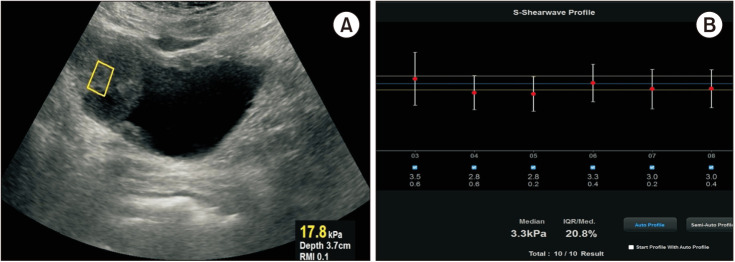

Materials and methods: Patients with microscopic or macroscopic hematuria diagnosed with bladder tumors were included. SWE measurements were performed using a Samsung Medison RS80A Prestige ultrasonography device, with ten valid measurements taken for each tumor. Tumor specimens were collected via transurethral resection (transurethral resection of the bladder tumor) for histopathological analysis. Microvessel density (MVD) was assessed by immunohistochemical staining with anti-CD34 antibody using the hot-spot method. Correlations between tissue stiffness, MVD and tumor stage and grade were analyzed, and receiver operating characteristic (ROC) analysis determined the optimal SWE cutoff for differentiating tumor characteristics.

Results: A total of 65 bladder urothelial carcinoma patients were included in the study (43 high-grade, 22 low-grade). SWE and MVD were significantly higher in the high-grade group (p=0.001, p=0.002, respectively). ROC analysis showed SWE could differentiate tumor grades (area under ROC curve=0.837, p<0.001), with a cut-off of 4.25 kPa (74% sensitivity, 86% specificity). Stiffness was also higher in recurrence (p=0.007). A strong positive correlation between SWE and MVD was found (rho=0.767, p<0.001). SWE may be a reliable, non-invasive tool for assessing tumor grade and recurrence risk.